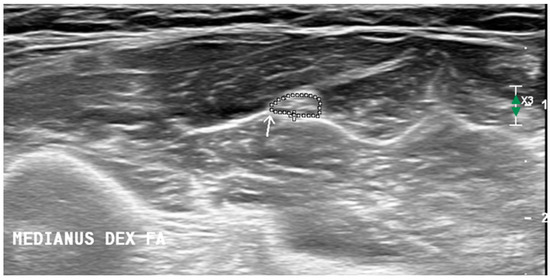

To make echogenicity evaluation more objective, quantitative image analysis using ImageJ (National Institutes of Health, Bethesda, MD, USA), version 1.54d was performed. The same nerve boundaries were used for measuring CSA, avoiding white dots access into the area being measured. Then native images were converted into 8-bit images while ImageJ software transacted each pixel in a range between 0 (black) and 255 (white) (Figure 2). After that, the threshold function was used, and the hyperechoic volume or fraction of white was calculated automatically. The fraction of black was calculated by subtracting the fraction of white from 100 [2]. For echogenicity evaluation, only unilateral images were analyzed.

Figure 2.

Arrow is pointing to the median nerve at the forearm. Image converted into an 8-bit image, each pixel in a range calculated between 0 (black) and 255 (white).